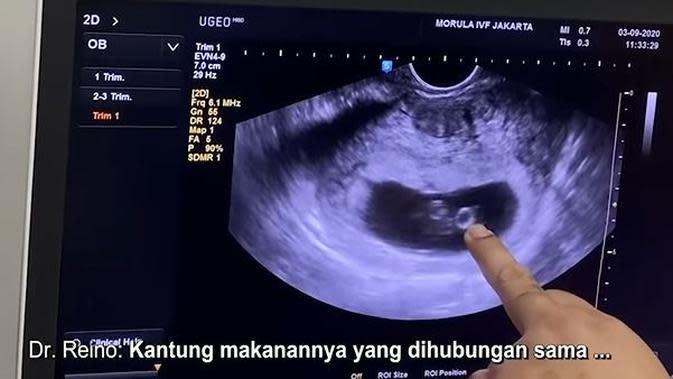

USG bayi 2 dimensi usia 9 minggu - YouTube

USG bayi 2 dimensi usia 9 minggu - YouTube

USG untuk Pemeriksaan Kehamilan 2 Bulan ~ DOKTER OZ INDONESIA 26 Februari 2017 - YouTube

USG untuk Pemeriksaan Kehamilan 2 Bulan ~ DOKTER OZ INDONESIA 26 Februari 2017 - YouTube

USG dasar dalam kehamilan

USG dasar dalam kehamilan

USG dasar dalam kehamilan

USG dasar dalam kehamilan